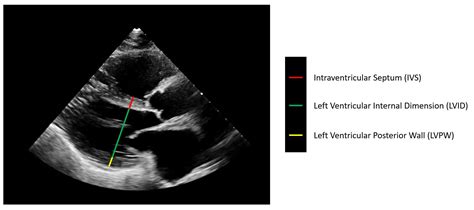

Ekokardiogram (Echo)

Ini adalah gold standard untuk mendiagnosis LVH. Ekokardiogram menggunakan gelombang suara untuk membuat gambar bergerak jantungmu. Dokter bisa melihat dengan jelas ukuran dan ketebalan dinding ventrikel kiri, bagaimana katup jantung berfungsi, dan seberapa baik jantung memompa darah. Dari echo, kita bisa membedakan antara hipertrofi konsentris dan eksentris.

Echocardiogram image of heart

Image just for illustration